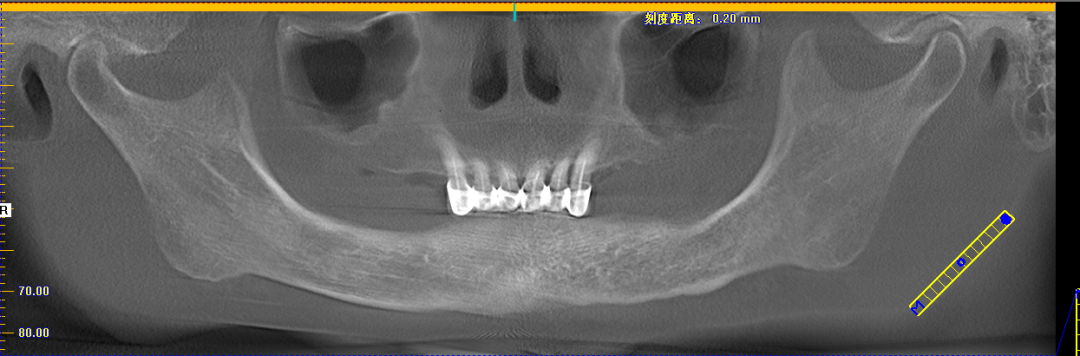

赖女士种牙后CT

姚江武院长来为大家分享顾客术前牙片情况及种植方案。并现场讲解数字化全程导板种植技术与传统种植牙的区别和优势。

传统种植牙手术,被称为“自由手种植牙”,需要种植医生具备丰富的临床经验,从而准确判断种植牙植入牙槽骨的角度、深度。而数字化种植牙,通过制作数字化种植导板,导航辅助种牙,引导种植体精准植入,不仅创口小更舒服,而且避免盲种,吻合度更高,使种牙全程精准、微创,轻松享受缺牙重生的乐趣。